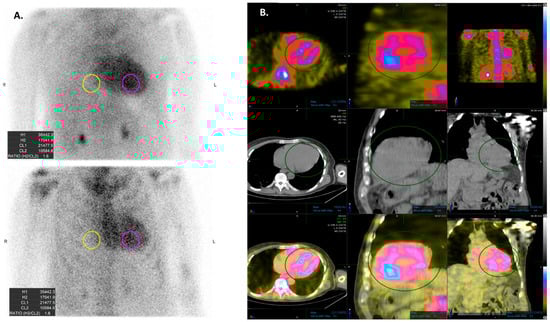

5. AI Applications to Scintigraphy in Cardiac Amyloidosis

- Halme, H.L.; Ihalainen, T.; Suomalainen, O.; Loimaala, A.; Matzke, S.; Uusitalo, V.; Sipila, O.; Hippelainen, E. Convolutional neural networks for detection of transthyretin amyloidosis in 2D scintigraphy images. EJNMMI Res. 2022, 12, 27. [Google Scholar] [CrossRef] [PubMed]

- Delbarre, M.A.; Girardon, F.; Roquette, L.; Blanc-Durand, P.; Hubaut, M.A.; Hachulla, E.; Semah, F.; Huglo, D.; Garcelon, N.; Marchal, E.; et al. Deep Learning on Bone Scintigraphy to Detect Abnormal Cardiac Uptake at Risk of Cardiac Amyloidosis. JACC Cardiovasc. Imaging 2023, 16, 1085–1095. [Google Scholar] [CrossRef] [PubMed]

| Grade 0 | No cardiac uptake. |

| Grade 1 | Mild cardiac uptake, less than that in ribs. |

| Garde 2 | Moderate cardiac uptake is similar to that in ribs, but uptake in ribs remains clearly visible. |

| Garde 3 | Intense cardiac uptake greater than that in ribs with weak or no signal evident in ribs. |